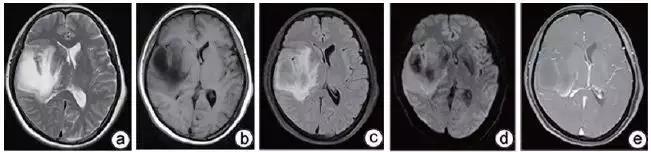

DPT 多为单发,偶为多发。发病部位为中枢神经系统任何部位,主要累及皮层下白质。表现为局灶性肿块,形态欠规则,边界不清,周围水肿明显,占位效应明显。病灶信号多较均匀,在 T1WI 上呈不均匀稍低信号,T2WI 上呈高信号,在 DWI 上可呈略低、等或略高信号,少数可合并囊变或出血,上述平扫 MRI 表现与脑内原发性及转移性肿瘤特别是脑胶质细胞肿瘤难以鉴别,容易误诊。在 MRI 增强扫描上,由于 DPT 病灶常破坏血-脑脊液屏障,病灶可出现不同程度强化,其强化表现具有特征性,病灶可呈环形、斑片形、团块形等多种强化方式。其中,最重要的影像学特征为「开环征」与「垂直征」。

由于 DPT 的 MRI 表现与胶质瘤及转移瘤有很多相似之处,因此,常常发生误诊。增强扫描对于 DPT 与脑肿瘤鉴别有一定价值,DPT 的特征性表现为「开环征」和「垂直征」,尤其是垂直征,对于 DPT 具有很高的提示价值。DPT 主要应与胶质瘤鉴别。低级别胶质瘤强化不明显,高级别胶质瘤强化明显,有明显的坏死、水肿及占位效应,而脱髓鞘性假瘤为开环样强化、轻到中度水肿,且 DPT 水肿有随病程进展而消退的特点。